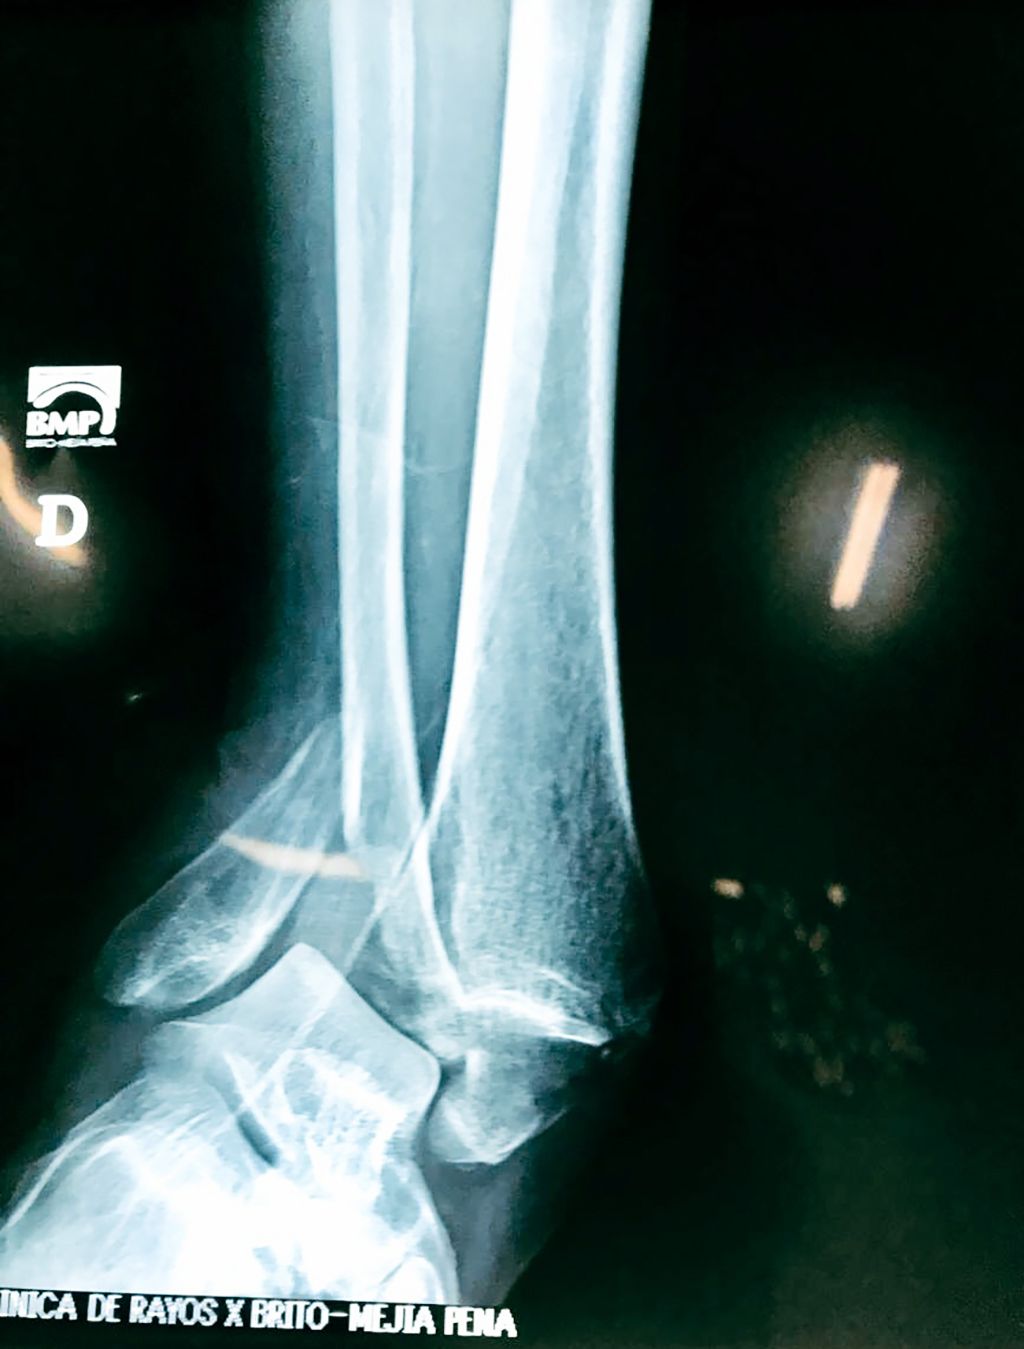

Una fractura de tobillo es la rotura de uno o más de los huesos del tobillo. Estas fracturas pueden ser:

Algunas fracturas de tobillo pueden requerir cirugía si:

- Los extremos de los huesos están desalineados entre sí (desplazados).

- La fractura se extiende hasta la articulación del tobillo (fractura intra-articular).